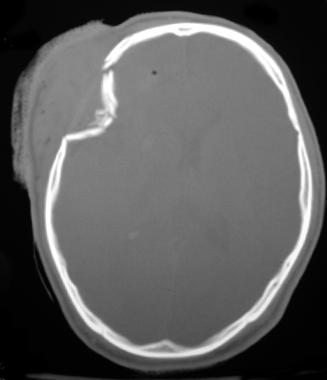

٥/ كسور عظام الجمجمه: يعالجها طبيب جراحة المخ والاعصاب.